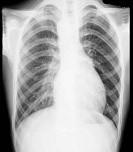

问题 21岁男性患者,劳累后心悸、气促5年,听诊第2肋间有喷射性杂音,胸部三位片如图所示,你认为正确的描述和答案是 ( )

选项 A、考虑房间隔缺损 B、考虑室间隔缺损 C、右前斜位示左心房食管压迹未见明显加深 D、左、右前斜位示右心房段延长 E、后前位示心脏左移,主动脉结缩小,肺动脉段突出

答案 ACDE